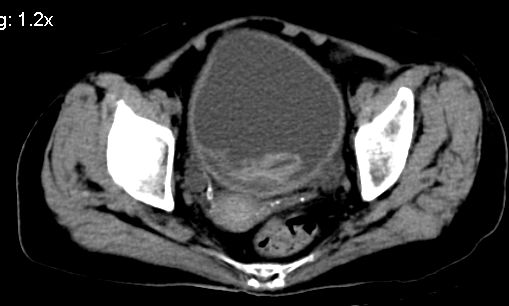

标题: CT10133:F、74岁,反复血尿10天。 [打印本页]

标题: CT10133:F、74岁,反复血尿10天。

膀胱充盈可,壁光滑厚薄尚均匀,其内下方可见不规则的致密影,建议做膀胱镜检查

膀胱癌突破浆膜可能性大

考虑膀胱癌可能性大伴双侧输尿管下端扩张.

膀胱后壁见不规则致密影,我们遇到这样的病人都再做一次俯卧位扫描;排出膀胱内凝血块。

1.膀胱后壁见不规则致密影,占位?膀胱内凝血块?建议俯卧位扫描、膀胱镜检查.

2.双侧输尿管下段扩张.

膀胱三角区不规整软组织改变,双侧输尿管扩张,所以占位性病变肯定首先考虑,建议改变体位扫描除外游离血块影,但老年人出血原因一定要查明。

1.膀胱后壁见不规则致密影,随体位改变,为膀胱内凝血块;

2.双侧输尿管下段扩张.输屎管结石可能大。建议作进一步检查。

双侧输尿管下端扩张,并膀胱内血凝块 输尿管下端结石